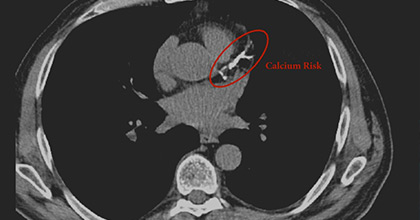

Descubre al Dr. Juan Díaz, cardiólogo experto en marcapasos y prevención, dedicado al cuidado integral de tu corazón.

Prevención, diagnóstico y tratamiento de enfermedades cardiovasculares. Médico, Docente e Investigador.